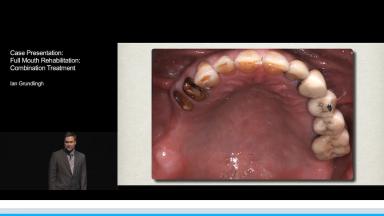

Case Presentation: Full Mouth Rehabilitation - Combination Treatment

The rehabilitation of a partially dentate patient with a skeletal and dentate Class III relationship remains a challenge. The concerns raised by this patient were aesthetics and loss of function. He had a history of chronic sinusitis and was smoking at least ten cigarettes per day. The intra oral examination revealed loss of posterior teeth due to caries, which resulted in severe bone loss, loss of occlusal vertical dimension and compromising the anterior aesthetics.